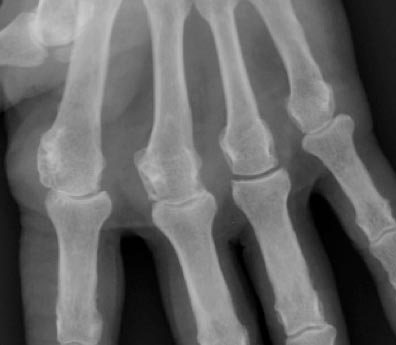

© La Revue du Praticien Radiographie de main gauche de face. Chondrocalcinose articulaire. Pincement de l'interligne des deuxième, troisième et cinquième métacarpophalangiennes.